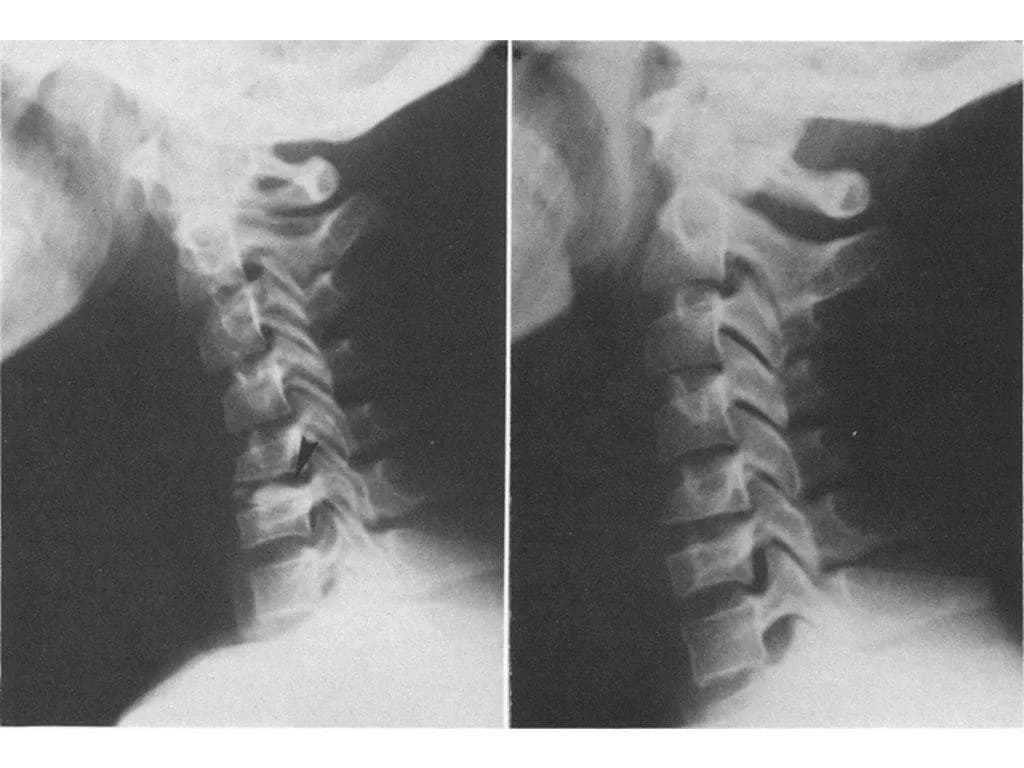

The effectiveness of conservative therapy in the treatment of pediatric intervertebral disc calcification (PIDC) was examined in 149 cases. A total of 109 patients had just one PIDC, 29 had two, and 21 had several. All patients received non-surgical, conservative care. After neck traction or collar fixation, all patients' symptoms disappeared. These findings indicated that PIDC can be treated conservatively.